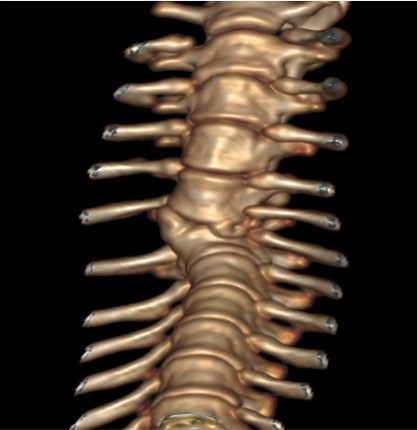

CT는 신체의 여러 각도에서 x-선을 투과시킨 후 단면 영상과 3차원적 입체영상을 얻을 수 있어 해부학적 구조와 병적 변화 정도를 정확하고 빠르게 평가할 수 있습니다.

CT 검사는 각종 종양과 염증, 외상 및 신체 기형과 같은 질환의 진단에 유용하게 사용될 수 있으며 수술이 지시되는 경우에도 진단을 넘어 정확한 해부학적 구조의 평가가 가능해져 이를 통해 수술 계획을 수립할 수 있습니다.

건국대학교 동물암센터에서 보유하고 있는 CT는 여러 개의 디텍터를 갖고 있는 multi-detector CT (MDCT)로써 촬영 시간 및 피폭량을 최소화 할 수 있는 장점이 있습니다. 여러 개의 디텍터를 통해 선명한 영상을 빠르게 구현해 냄으로써 진단의 정확성을 높일 수 있습니다.

- 골격계 질환 및 골절 합병증 평가

- 척추 질환 (척추 골절, hemivertebra)

척추질환